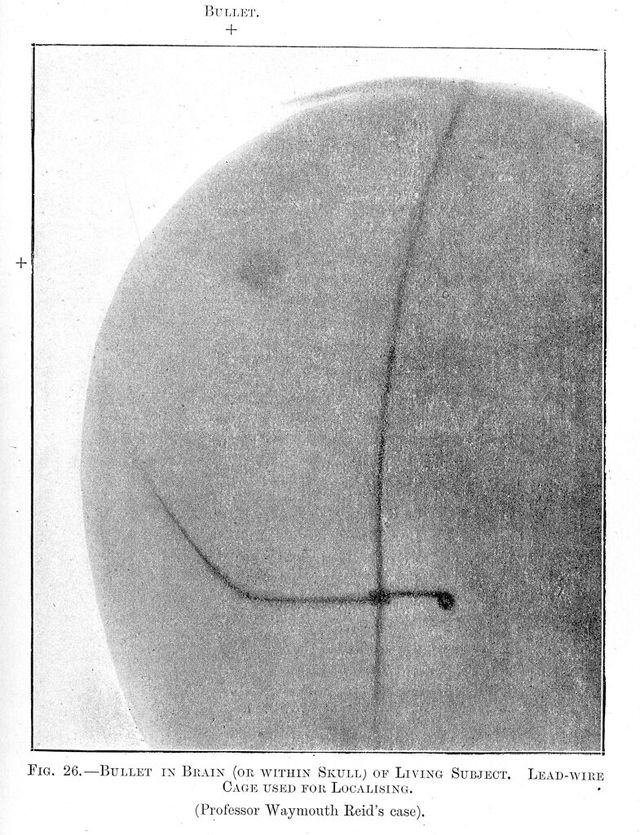

M0013196: Radiograph showing a bullet in the brain of a living subject

Credit: M0013196: Radiograph showing a bullet in the brain of a living subject. Source: Wellcome Collection.